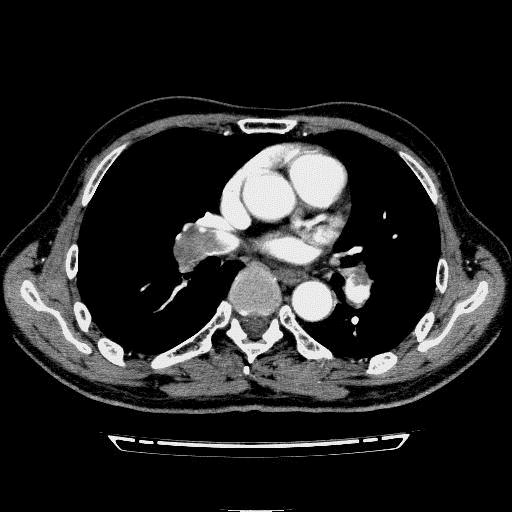

问题 病历摘要: 患者女性,83岁,活动后气促10天,伴心悸、咳嗽,咳少许白粘痰,感左侧胸痛,呈压榨样,与呼吸有关,但无放射痛,并发热,体温最高37.9℃,无明显规律性,无咯血、畏寒等。既往有系统性红斑狼疮病史,有吸烟史20年,已经戒烟20年。1月前始自觉双下肢易疲劳,但活动不受限。体查:T37.7℃,左肺可闻及啸鸣音和少许细湿啰音,心率123bpm,律齐,P2>A2,未闻及杂音。双下肢无水肿。 肺血栓栓塞症的X线胸片主要有哪些表现?

选项 A.区域性肺纹理变细、稀疏或消失 B.肺野透亮度增加 C.右心室扩大 D.肺动脉段突出 E.肺野局部片状影 F.右下肺动脉干增宽或伴截断征 G.尖端指向肺门的楔形影 H.少到中量胸腔积液

答案 ACDEFGH